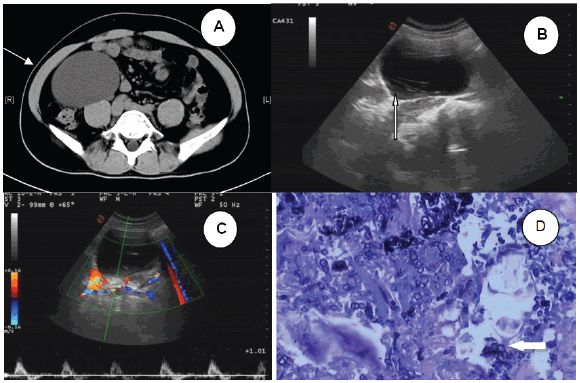

图1 (A)腹部CT扫描显示右腹膜后囊肿肿块(箭头) (B)超声检查显示囊肿内部低回声区周围边缘模糊的带状高回声病灶(箭头) (C)CDFI未见明显血流信号 (D)术后病理示钙质微粒和蠕虫组织(箭头)

2016年5月,中南大学湘雅医学院附属海口医院收治了一位患者。患者男性,42岁,工作稳定(小学教师),未去过海外。3月前,体检偶然发现右上腹部囊性肿块。腹部CT扫描显示右腹膜后囊肿肿块,信号强度低,边界清晰,大小约为9.4×7.6×9.2cm,增强CT未见异常。肿块紧靠右肾下部,且部分升结肠向左移位(图1A)。患者无发烧、腹痛等症状,其它体检指标均正常。研究人员初步影像学诊断为淋巴囊肿,告诉患者有必要进一步检查和治疗,但患者还是拒绝并出院回家。

患者于2016年8月再次来院就诊,希望手术切除肿块。入院时复查超声示右上腹部囊性肿块,肿块内可见带状高回声病灶,周围低回声区边缘模糊。彩色多普勒血流显像(CDFI)显示内侧未见明显血流(图1B C)。这次,患者也无发烧、腹痛等症状,其它体检指标均正常。然而,接诊医师未发现两次检查结果差异,且缺乏怀疑,故给出了同样的诊断。

术后病理报告为sparganosis,其中部分囊壁为输尿管组织,免疫组化显示SMA(+),S-100(-),Vim(+),HMB45,CD68(-)(图1D)。术后实验室检查:白细胞计数16.16×109/L,中性粒细胞比例增加(14.8%),C反应蛋白23.2mg/dl。在给予吡喹酮两个疗程后,患者所有实验室指标均在正常范围,出院时伤口愈合良好。1月后,患者无任何不适,血常规、尿常规、肝功、肾功均正常。随后,研究人员通过膀胱镜取出双J管。Sparganum(裂头蚴)血清抗体滴度为阴性,盆腔、腹部超声中均未发现异常。术后患者每3月复查1次,随访近1年未发现异常。